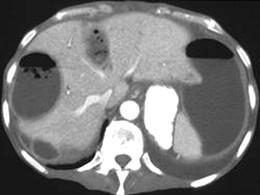

问题 男,67岁,右上腹痛、腹胀,右季肋区叩击痛,体温39℃,CT检查如图,最可能的诊断是 ( )

选项 A、肝转移癌 B、肝淋巴管瘤 C、多发性肝脓肿 D、肝包膜下出血伴囊变 E、多发性肝囊肿

答案 C